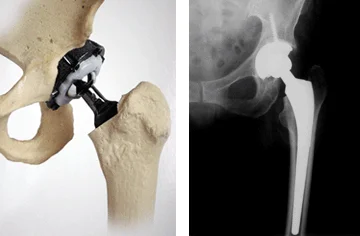

El problema se extiende hasta la edad adulta, por lo que el 3,5% de los adultos mayores de 55 años tienen artrosis de cadera, atribuyéndose el 50% de ellas a displasias congénitas.

La reducción abierta de la cadera esta indicada cuando la reducción cerrada no logra su objetivo de obtener una cadera concéntrica, estable y sin tejidos interpuestos